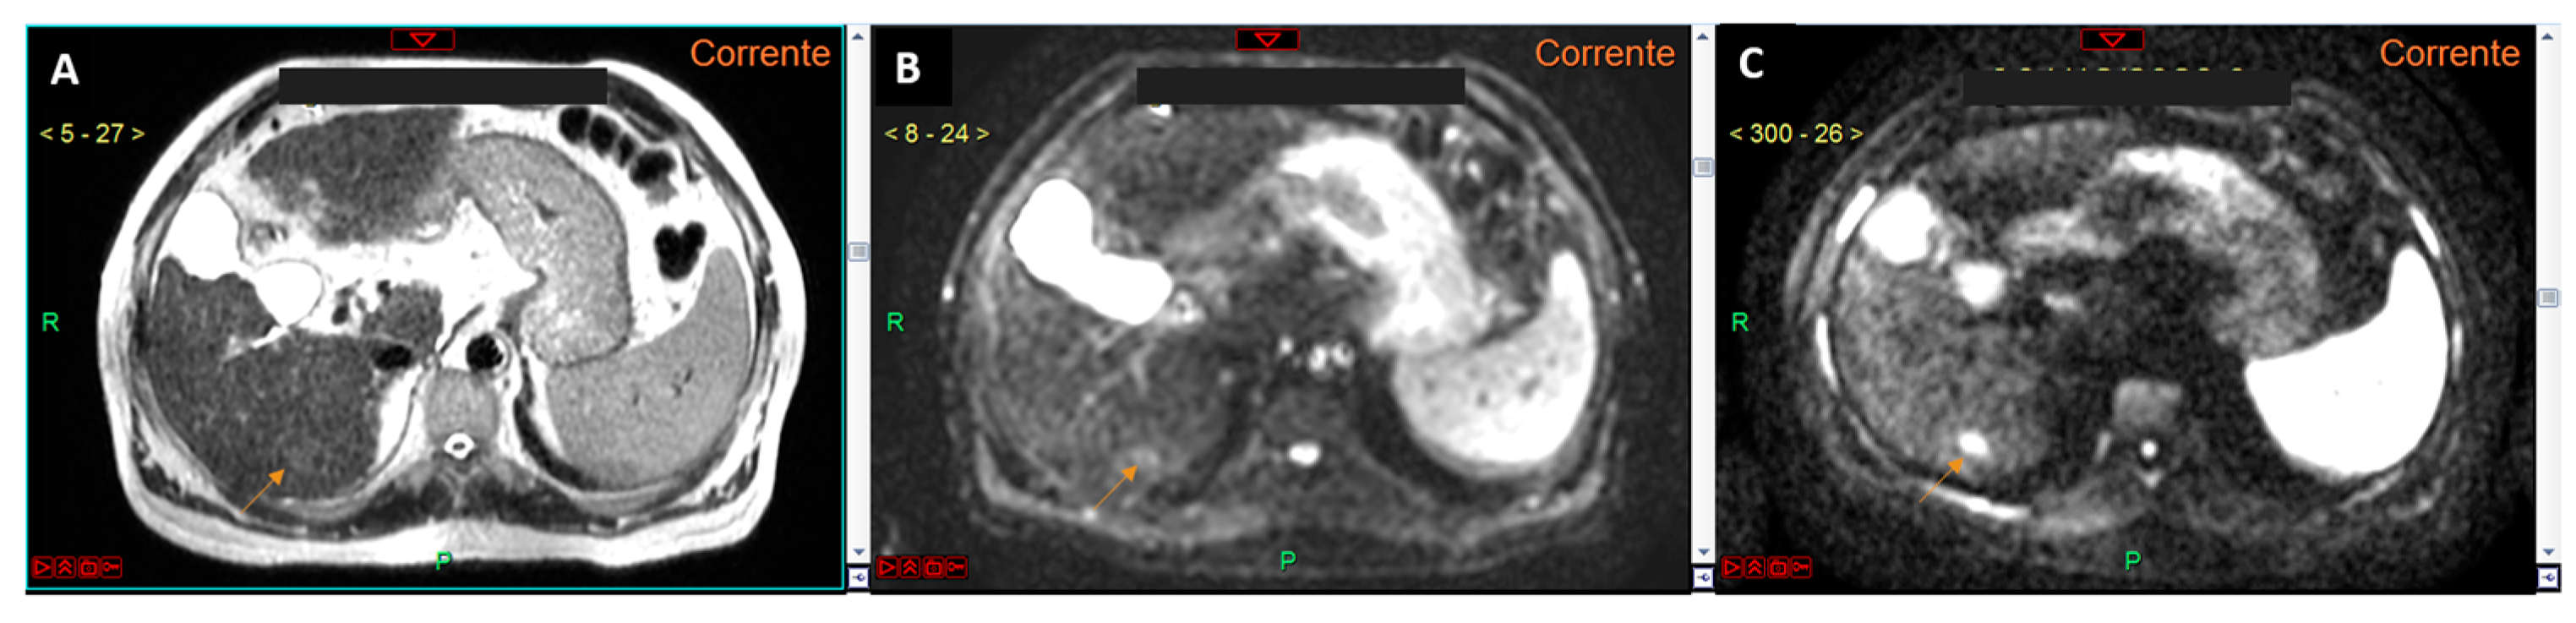

- Non-contrast aMRI (NC-aMRI): This protocol includes T1 in-phase and out-of-phase sequences, T2-weighted sequences, and diffusion-weighted imaging (DWI) with b0 and a single high b-value;

- Dynamic aMRI (D-aMRI): This protocol involves volumetric T1-weighted imaging during the pre-contrast phase and three dynamic (arterial, portal, and delayed) phases using an extracellular contrast agent;

- Hepatobiliary phase (HBP) aMRI (HBP-aMRI): This protocol uses hepatospecific contrast agents, with imaging performed approximately 20 min post-injection. It includes T2-weighted sequences, DWI with b0 and another single high b-value, and the hepatobiliary phase.